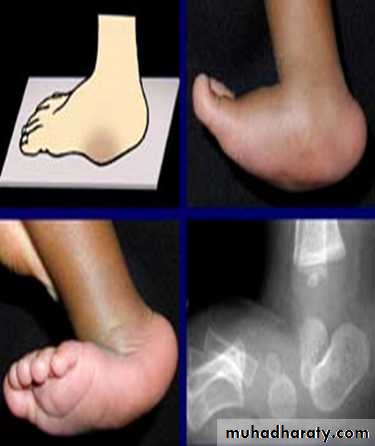

Congenital vertical talus:

Its rare and uncommon, it present at birth. The foot is convex on the sole (like the bottom of the rocker), the talus is vertically placed with dislocation of the talonavicular joint, the whole forefoot is dorsiflexed and valgus at the tarso-metatarsal region. Any attempt to correct this rigid deformity by manipulation is very difficult, it usually needs surgery and prognosis is poor.Spasmodic flat foot: